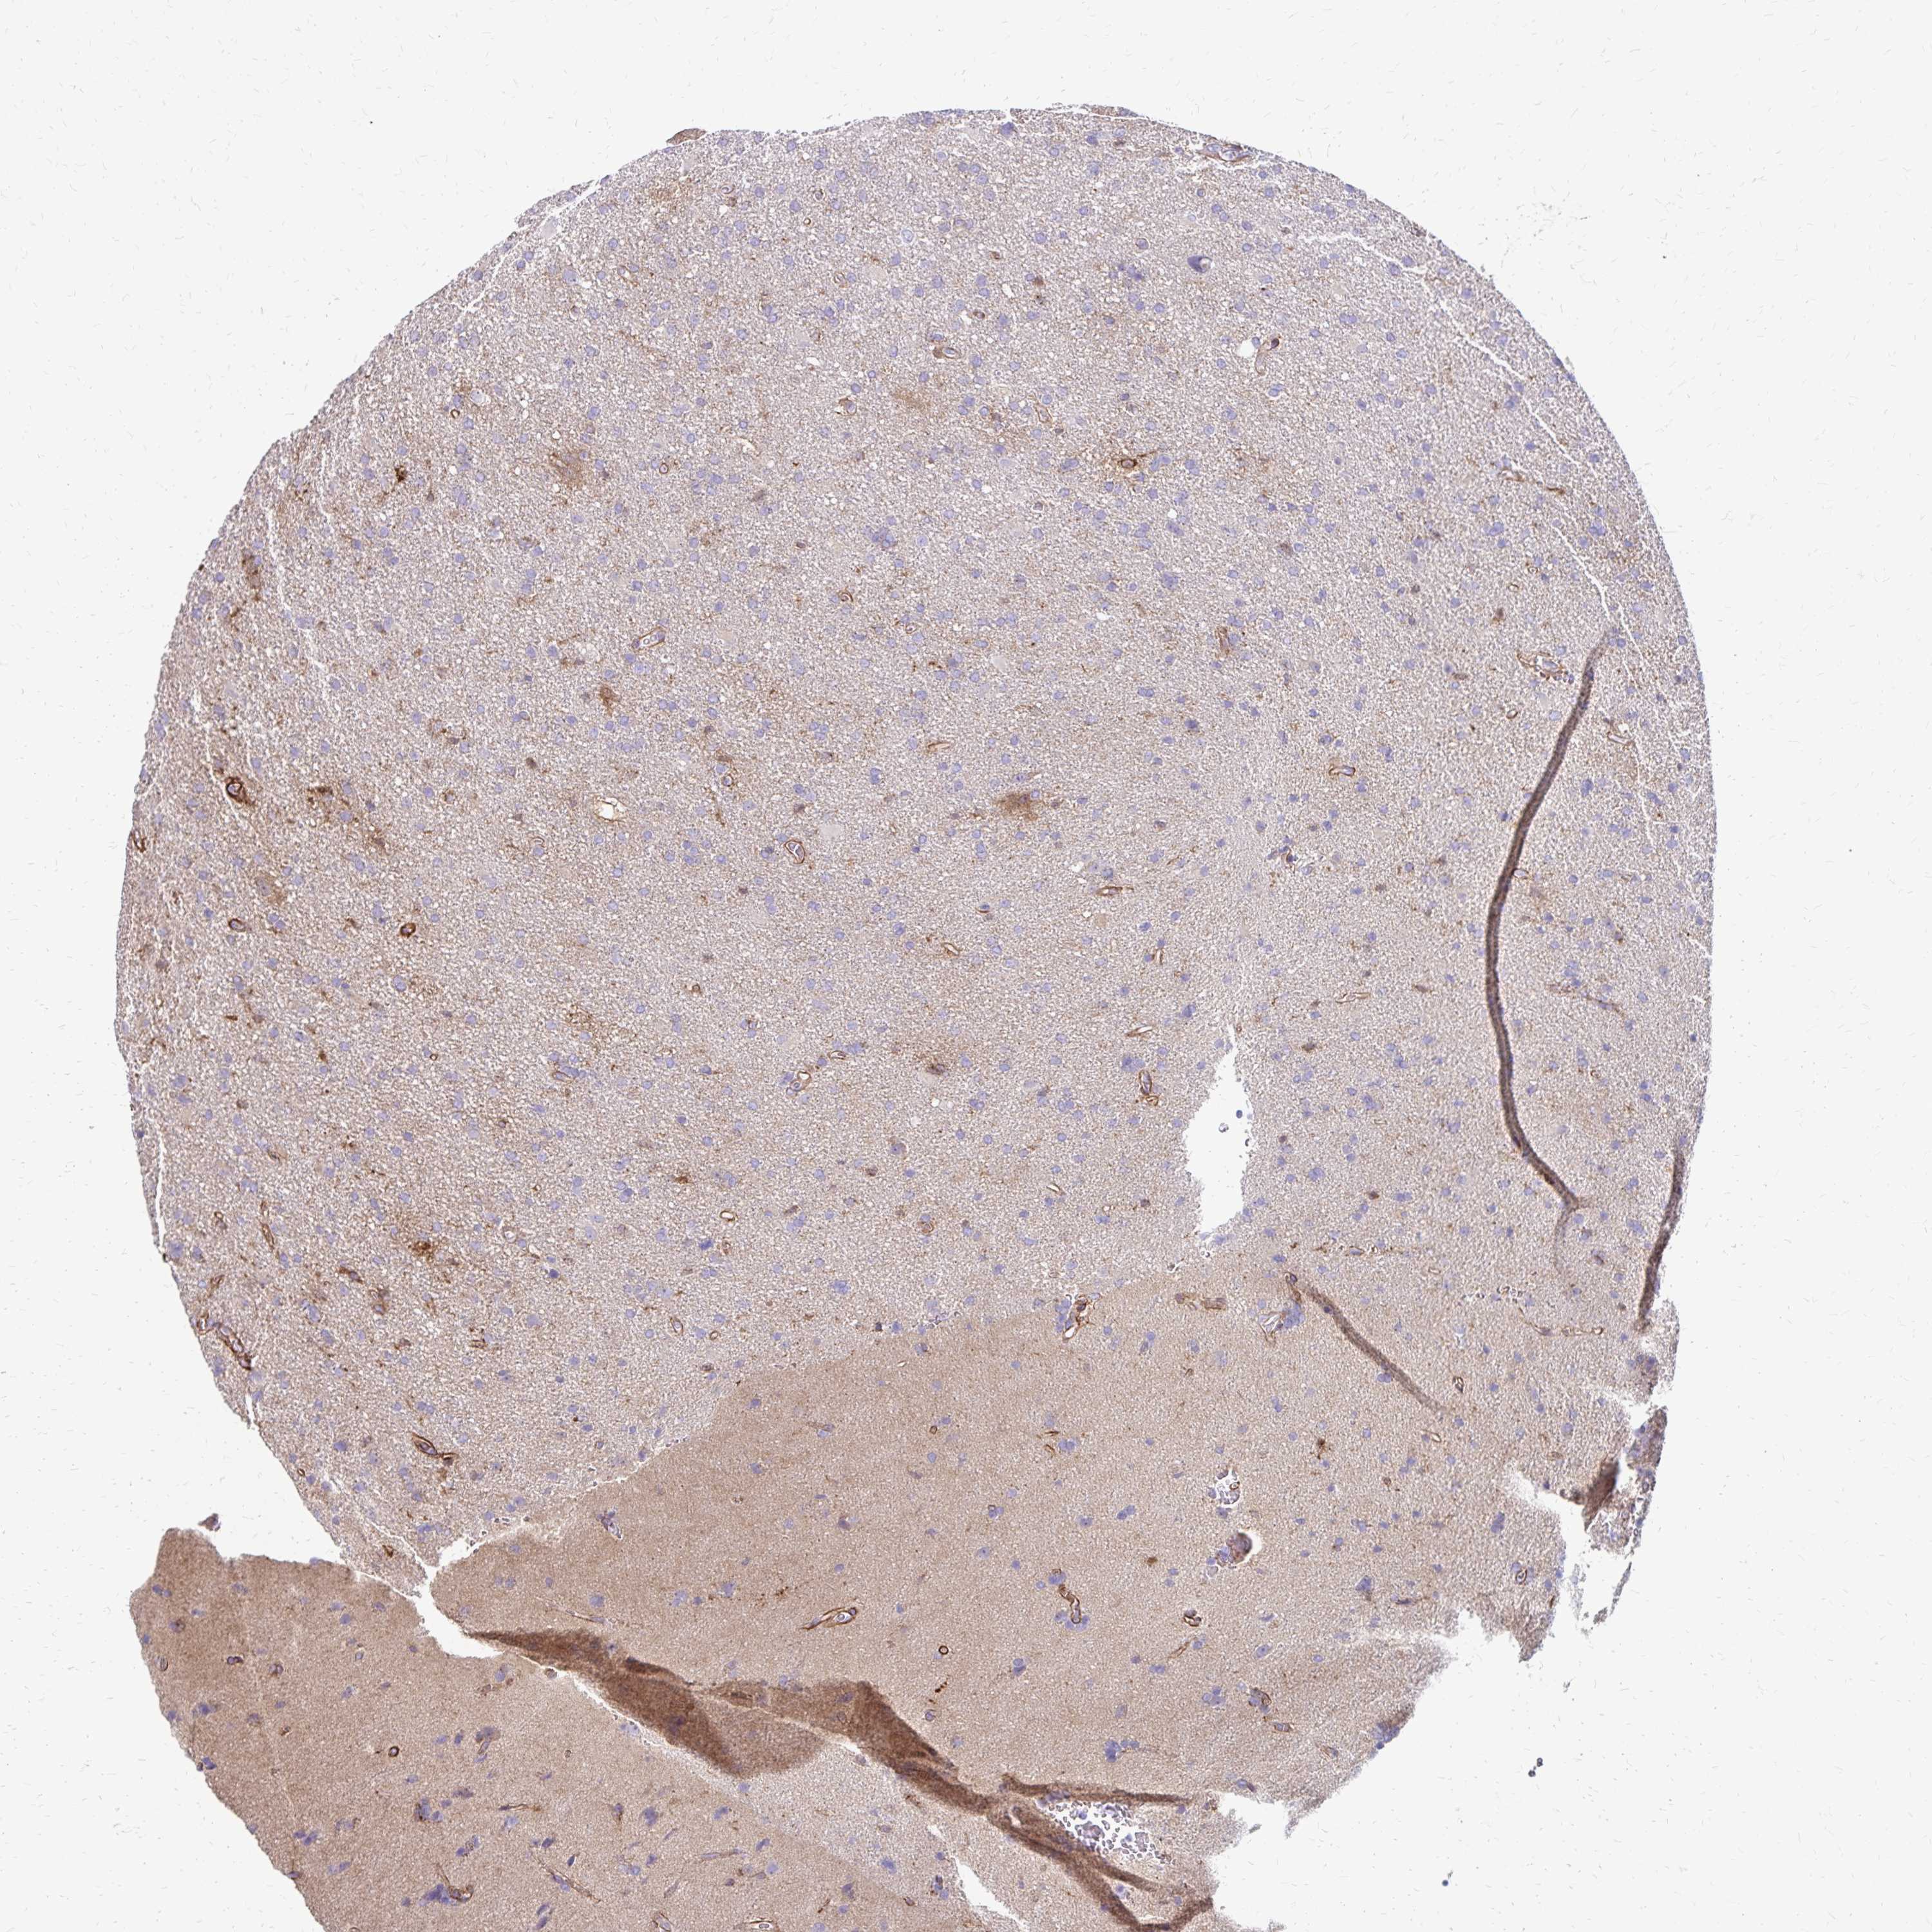

GLIOMA - Protein expressioni

A mouse-over function shows sample information and annotation data. Click on an image to view it in a full screen mode. Samples can be filtered based on level of antibody staining by selecting one or several of the following categories: high, medium, low and not detected. The assay and annotation is described here.

Note that samples used for immunohistochemistry by the Human Protein Atlas do not correspond to samples in the TCGA dataset.

Antibody stainingi

Antibody staining in the annotated cell types in the current human tissue is reported as not detected, low, medium, or high, based on conventional immunohistochemistry profiling in selected tissues. This score is based on the combination of the staining intensity and fraction of stained cells.

Each image is clickable and will lead to virtual microscopy that enables deeper exploration of all samples and also displays staining intensity scores, fraction scores and subcellular localization as well as patient and tissue information for each sample.

Antibody HPA055338

Antibody HPA056015

Staining

High

Medium

Low

Not detected

Intensity

Strong

Moderate

Weak

Negative

Quantity

>75%

75%-25%

<25%

None

Location

Nuclear

Cytoplasmic/membranous

Cytoplasmic/membranous,nuclear

Glioma, malignant, Low grade

Glioma, malignant, High grade